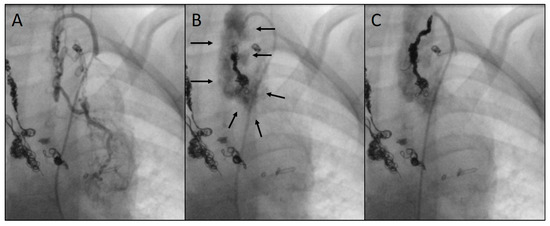

2.2. Catheterization and Transcatheter Embolization